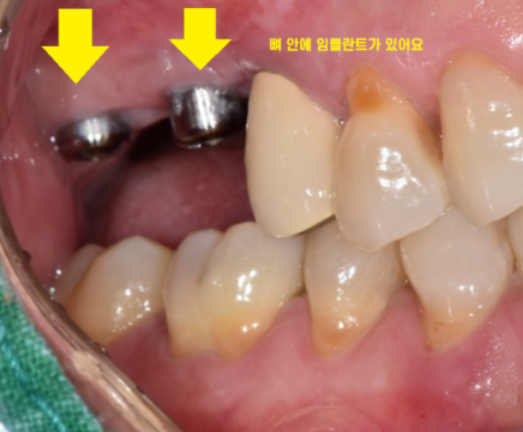

때문에 임플란트 수술을 하고 나면

머리 대신에 작은 나사만 연결해둡니다.

뼈가 거의 없는 경우에는

임플란트를 잇몸 안에 묻어두기도 하는데요.

이럴 경우에는 잇몸밖에 안느껴지기 때문에

임플란트 심은게 맞나.. 싶기도 합니다.

겉으로 봤을 때는 잇몸만 느껴지지만

x-ray를 보실까요~?

임플란트가 잘 심어져있습니다.